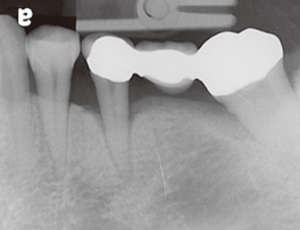

未經牙周病治療的牙齒,幾年後....

本院實例:

牙周病會造成牙齦發炎流血,齒槽骨牙周韌帶的破壞,最終導致牙齒的脫落。成人的牙齒脫落原因中有75%是因為牙周病造成的。